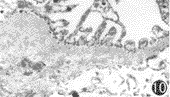

对照组:大鼠RBM和GBM的外疏松层可见排列较规则的多聚亚胺染色颗粒大小较一致,多聚亚胺染色颗粒代表负电荷位点存在的区域,负电荷位点主要由硫酸类肝素多糖蛋白构成(图9,10)。与RBM相比,GBM上的多聚亚胺染色颗粒数量多、分布密度大。

图9 对照组RBM负电荷位点分布情况 ×25000图10 对照组GBM负电荷位点分布情况 ×20000